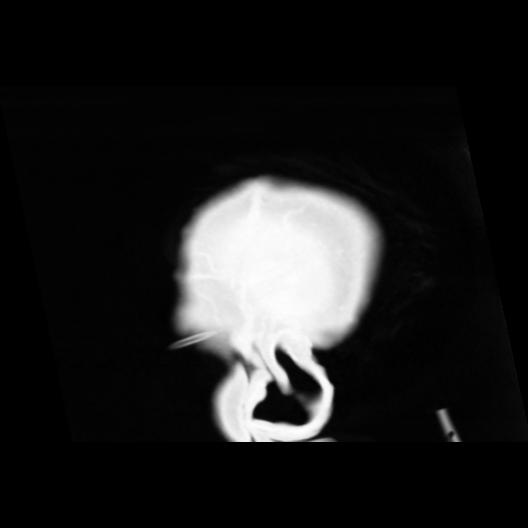

6 CEREBRO,,Sagittal,3.000,CEREBRO,Sagittal,